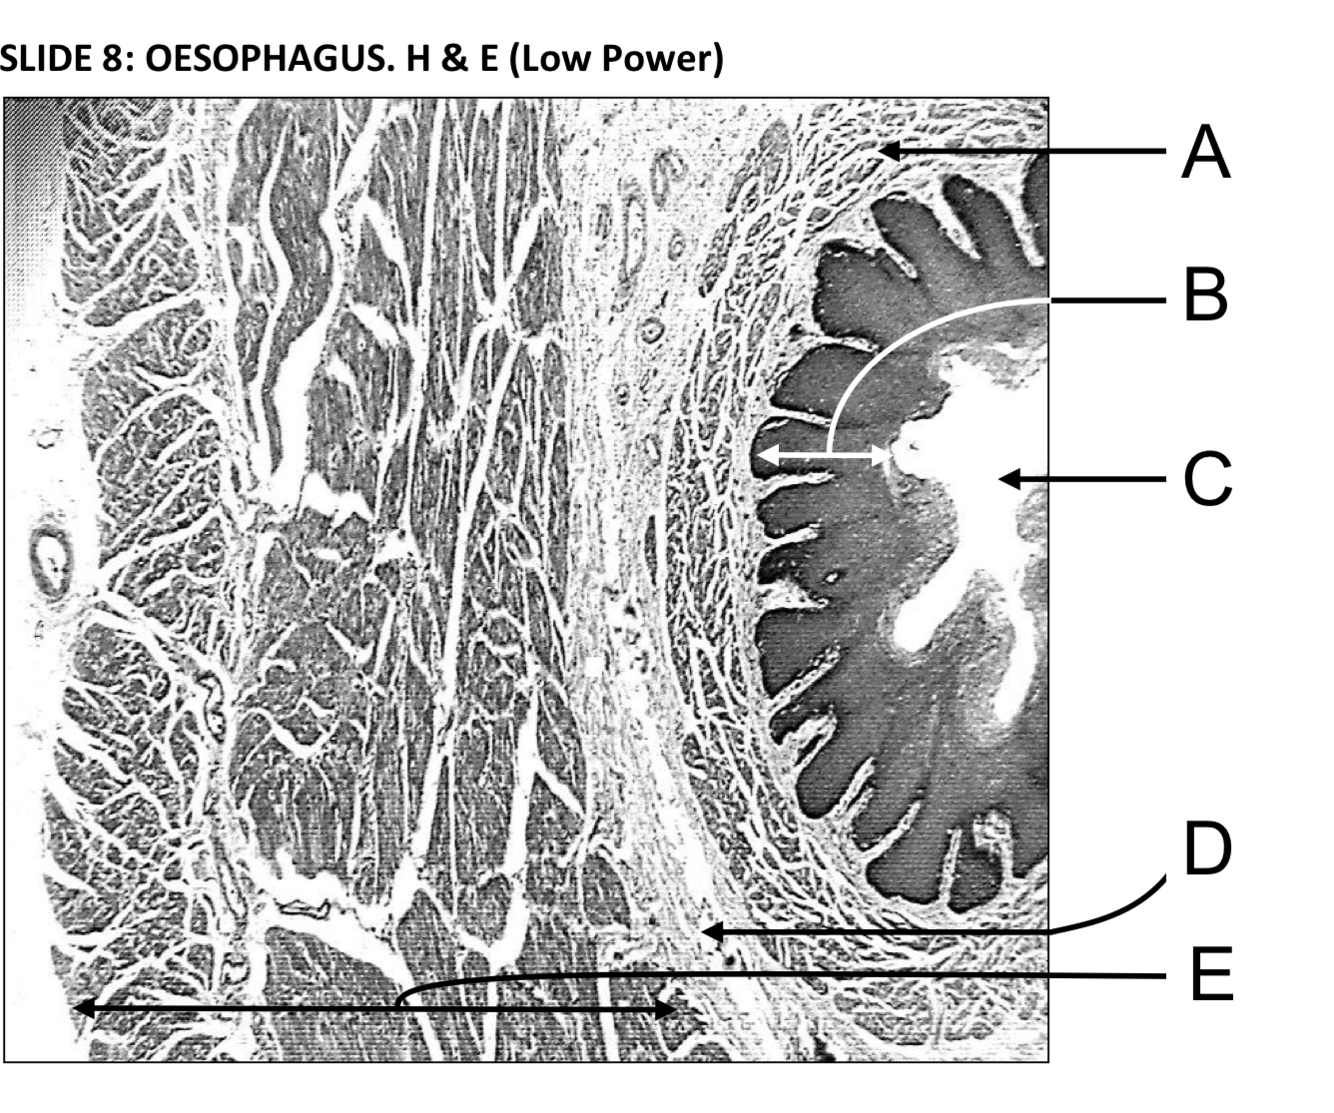

A - Muscularis mucosae (the muscular layer of this mucous membrane complex)

B - Stratified squamous non-keratinised epithelium

C - The oesophageal lumen is convoluted but opens up during swallowing

D - Submucosa - dense fibroelastic connective tissue containing glands

E - Muscularis externa - an outer longitudinal and an inner circular muscle laye. Can be a mixture of smooth and skeletal muscle